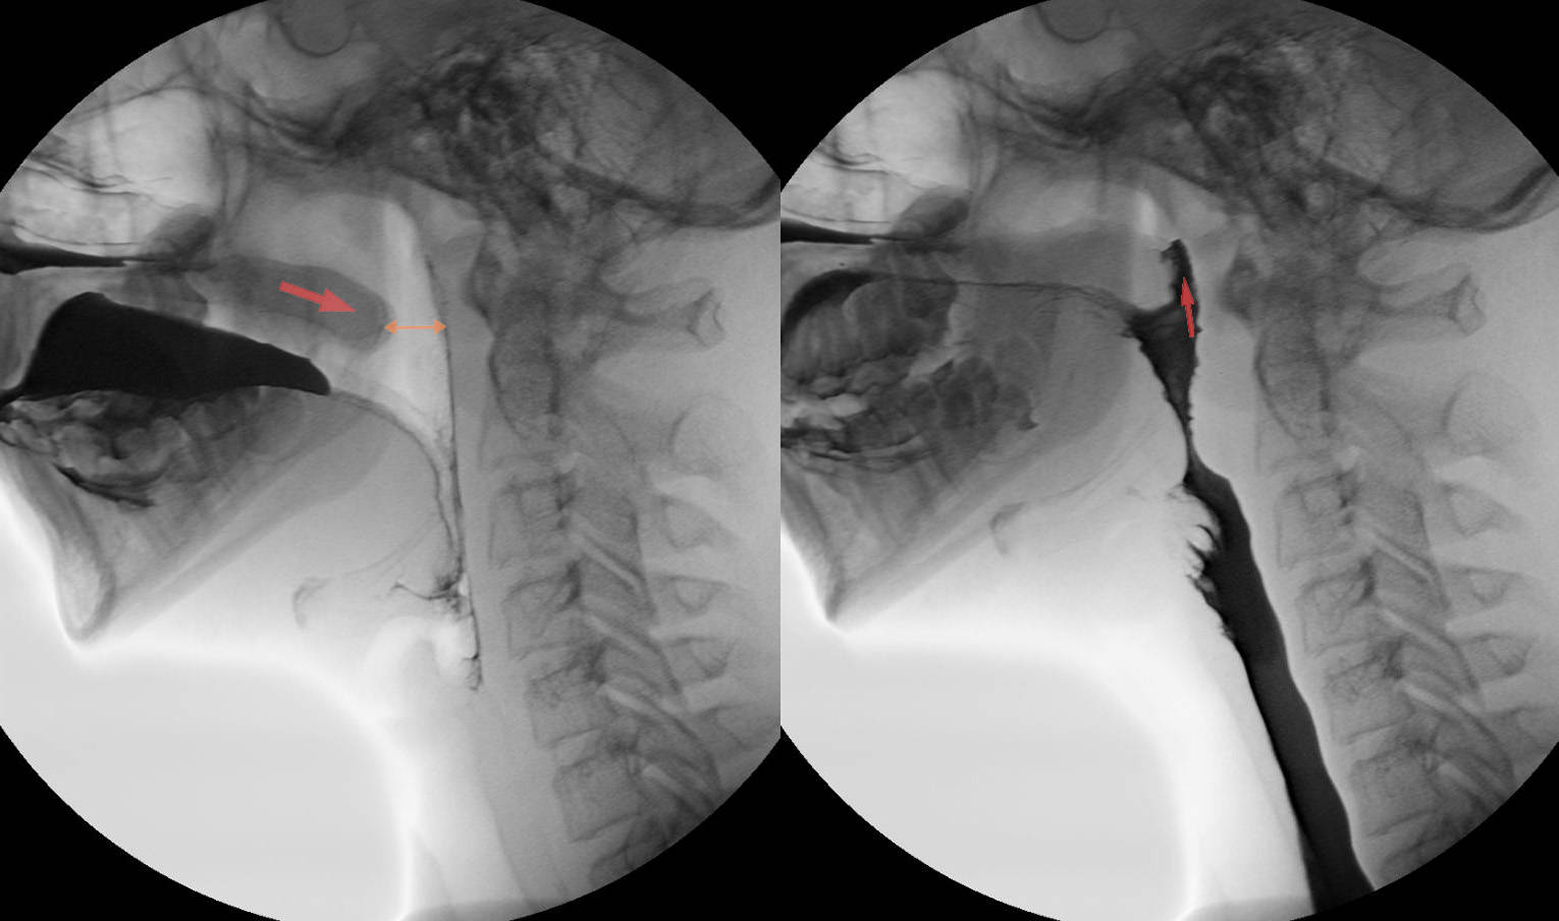

Medical image annotation is the process of labeling medical images, such as X-rays, MRIs, CT scans, and ultrasound images, to help AI models recognize patterns and abnormalities. This process involves trained radiologists, pathologists, and data annotators who precisely mark anatomical structures, tumors, and other critical elements within medical images.

2. Bounding Box Annotation

- Draws rectangular boxes around specific areas of interest in medical images.

- Helps in detecting abnormalities like fractures, tumors, and cysts.

4. Keypoint Annotation

- Marks specific points in a medical image, such as joint locations in orthopedic scans.

- Assists in tracking anatomical changes over time.